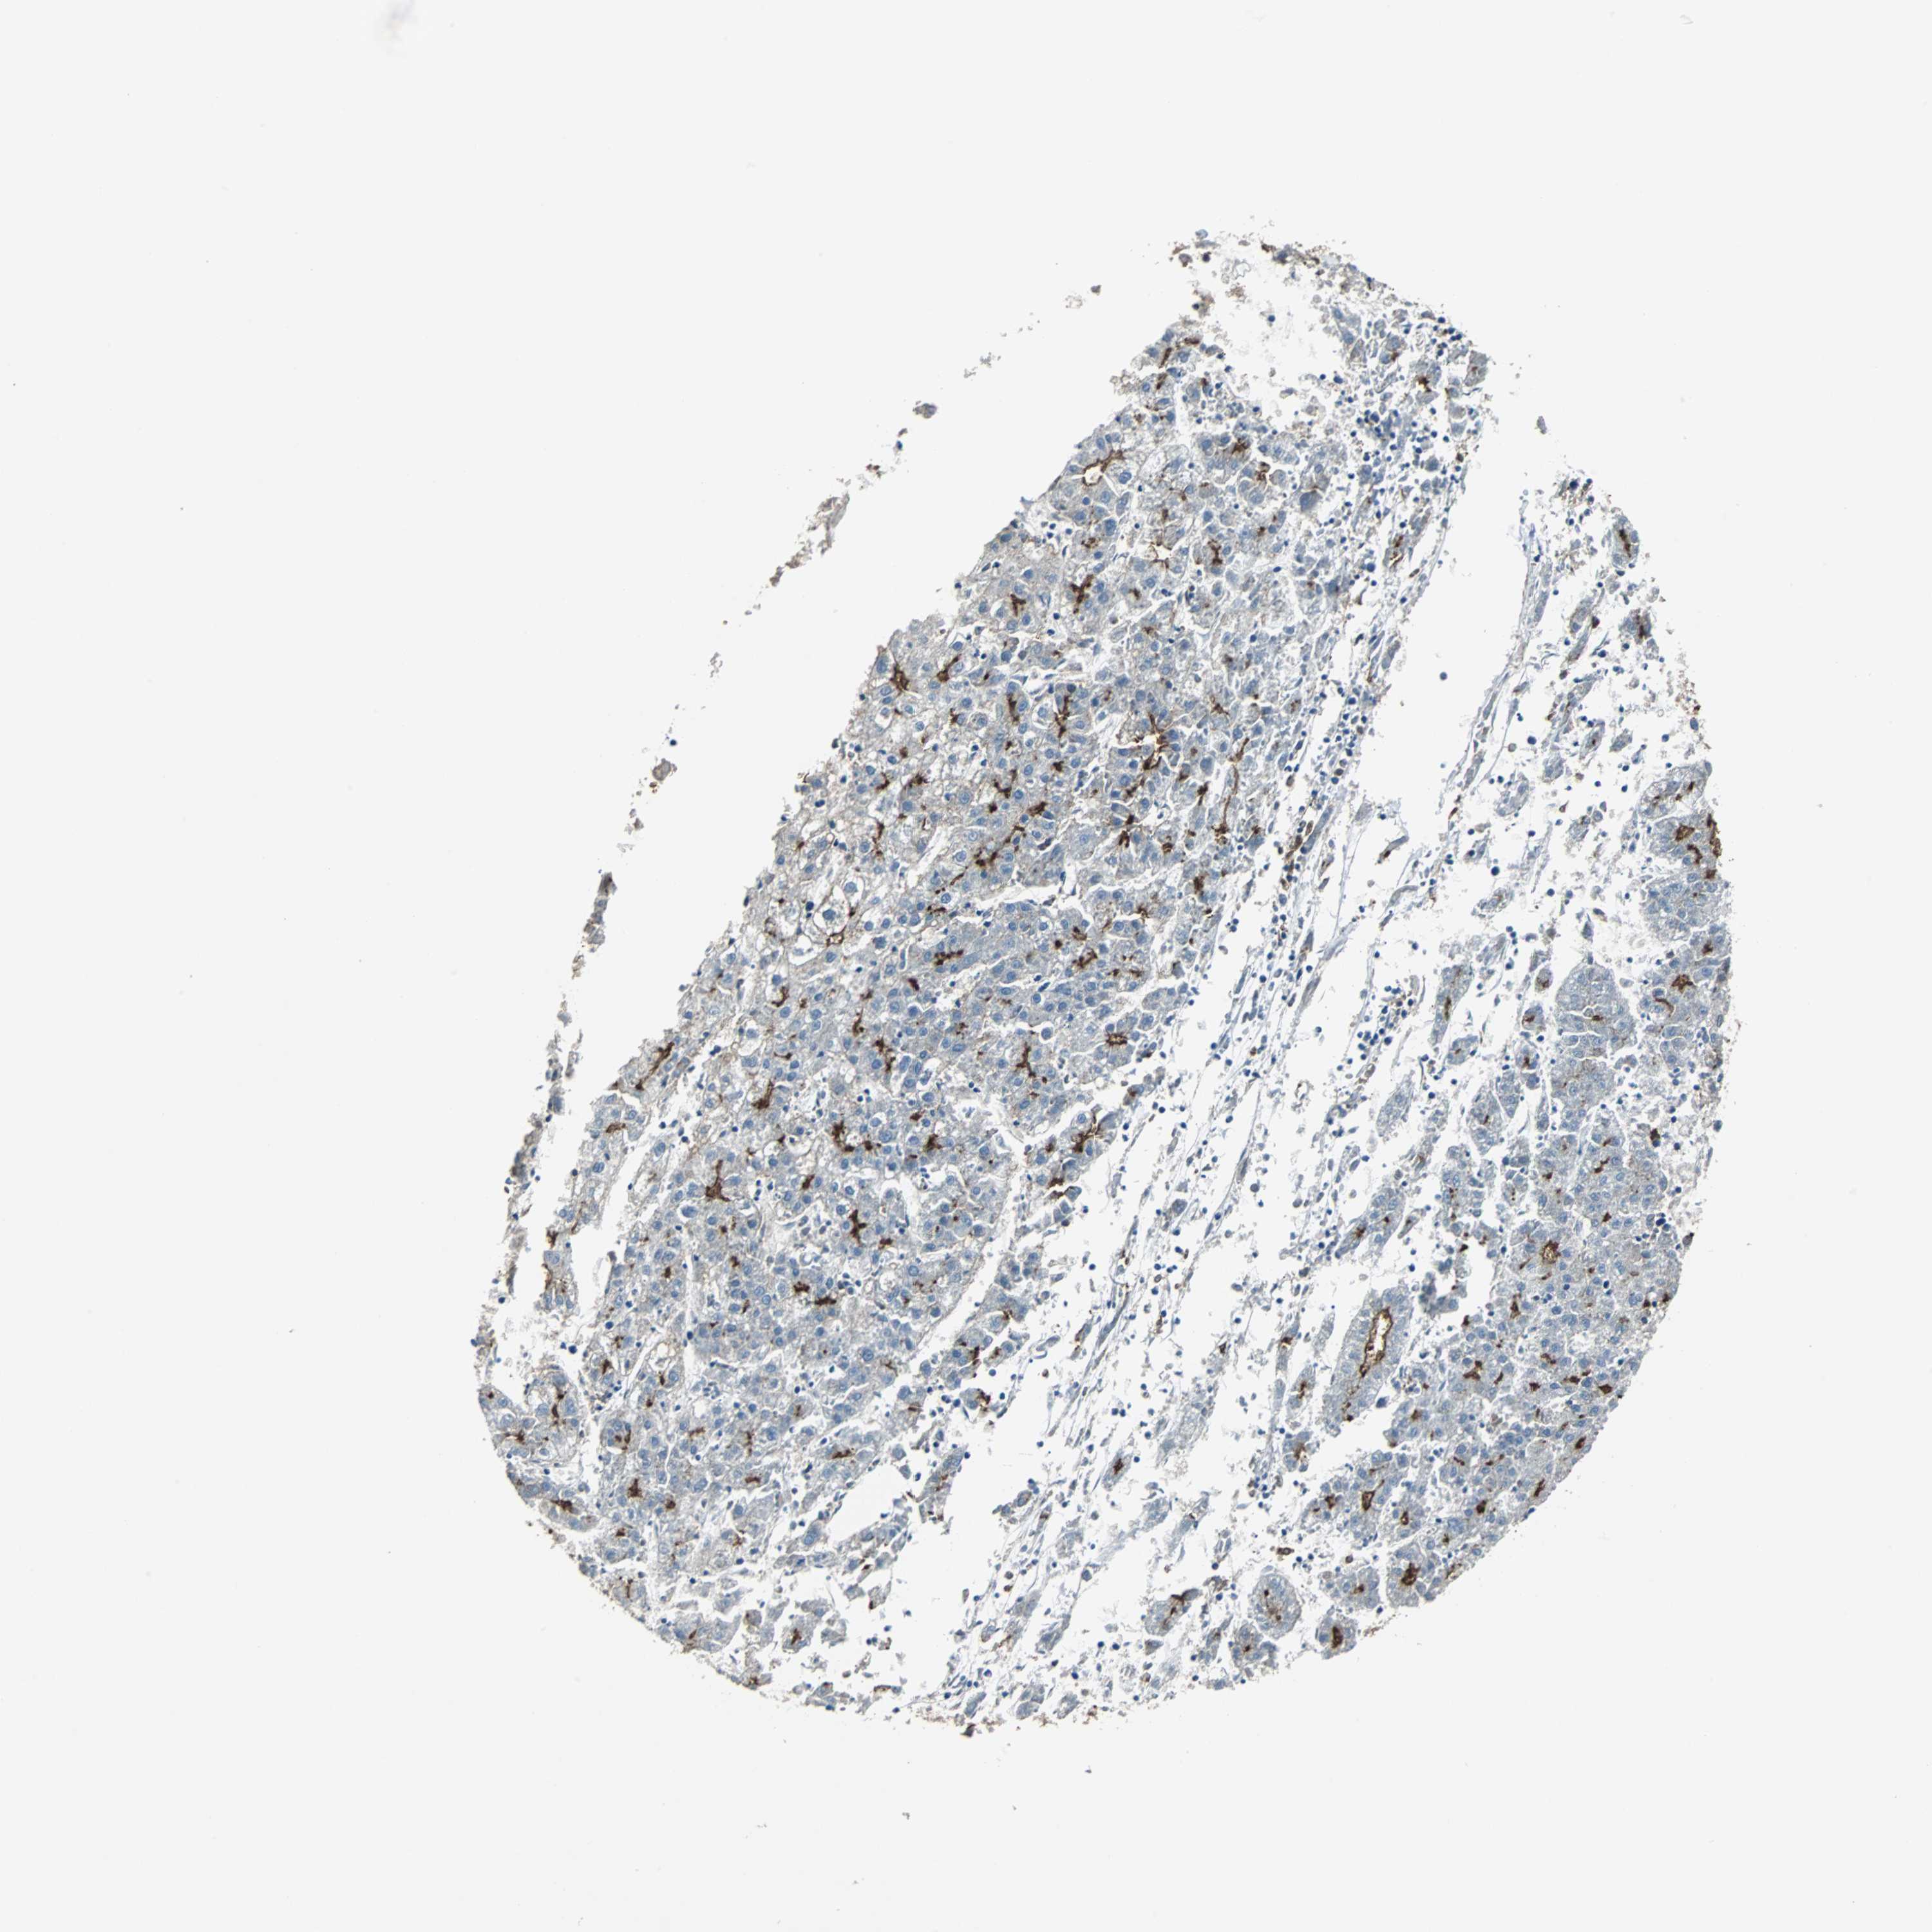

LIVER CANCER - Protein expressioni

A mouse-over function shows sample information and annotation data. Click on an image to view it in a full screen mode. Samples can be filtered based on level of antibody staining by selecting one or several of the following categories: high, medium, low and not detected. The assay and annotation is described here.

Antibody stainingi

Antibody staining in the annotated cell types in the current human tissue is reported as not detected, low, medium, or high, based on conventional immunohistochemistry profiling in selected tissues. This score is based on the combination of the staining intensity and fraction of stained cells.

Each image is clickable and will lead to virtual microscopy that enables deeper exploration of all samples and also displays staining intensity scores, fraction scores and subcellular localization as well as patient and tissue information for each sample.

Antibody HPA006927

Staining

High

Medium

Low

Not detected

Intensity

Strong

Moderate

Weak

Negative

Quantity

>75%

75%-25%

<25%

None

Location

Nuclear

Cytoplasmic/membranous

Cytoplasmic/membranous,nuclear

Cholangiocarcinoma

Carcinoma, Hepatocellular, NOS